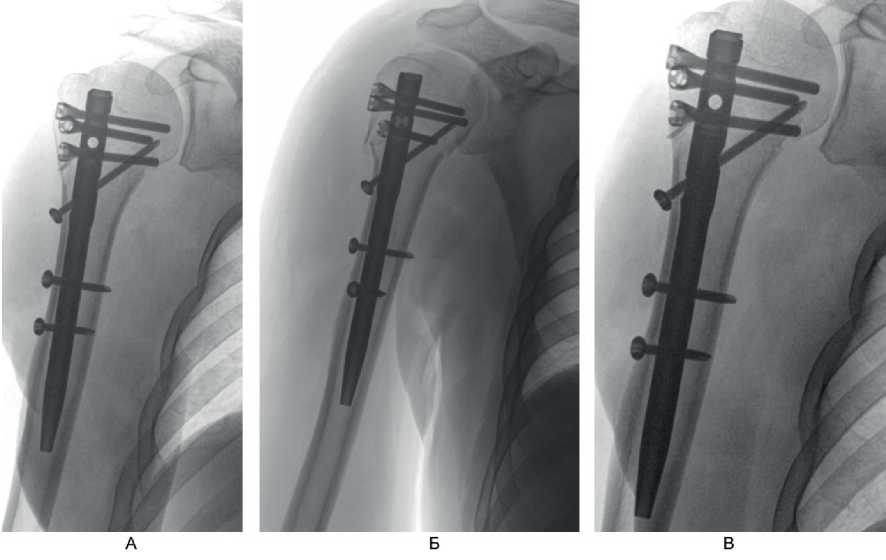

Клинический пример 2. Больной А., 50 лет, поступил в клинику ВЦЭРМ им. А.М. Никифорова в экстренном порядке. Выполнены рентгенография плечевого сустава в стандартных проекциях (рис. 8А), и компьютерная томография (см. рис. 8Б).

Рис. 8. Больной А., 50 лет. А – рентгенография плечевого сустава в стандартных проекциях; Б – компьютерная томография до операции

Перелом по классификации АО – С3.1. На 2-е сутки после поступления выполнено оперативное вмешательство – БИОС хирургической шейки правой плечевой кости. Рентгенография на 1-е сутки после операции представлена на рис. 9А, Б, контрольная рентгенография плечевого сустава через 6 мес после операции – на рис. 9В. Функциональный результат после операции – на рис. 10.

Рис. 9. Больной А., 50 лет. А, Б – рентгенография на 1-е сутки после операции; В – через 6 мес после операции